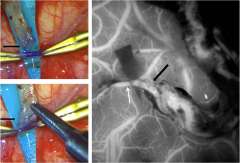

With an arteriovenous malformation, treatment decisions are nuanced and depend on whether the vessel has caused bleeding in the brain or not, says neurosurgeon Jeremiah Johnson, MD. “These complex tangles of blood vessels in the brain can rupture and cause hemorrhagic stroke,” explains Dr. Johnson. “The definitive treatment is surgery to remove the malformation, but sometimes that’s not possible due to location in the brain or other factors. For very deep or critical parts of the brain, for example, we often avoid surgery but may be able to treat with other modalities.”

If the blood vessel malformation hasn’t ruptured, ongoing monitoring can sometimes be the safest option, but each patient and each malformation is different. The preferred option to treat some AVMs may be stereotactic radiation, where radiation beams are tightly focused on the malformation but minimally impacting the surrounding normal tissues. Or it could involve embolization, or blocking off surrounding branches of the blood vessel to safely remove the malformation. UCLA provides individualized expert care for even the most complex cerebrovascular disorders. Both Dr. Johnson and Dr. Colby are dual-trained in endovascular and cerebrovascular open surgery techniques, with expertise to perform these multifaceted procedures.